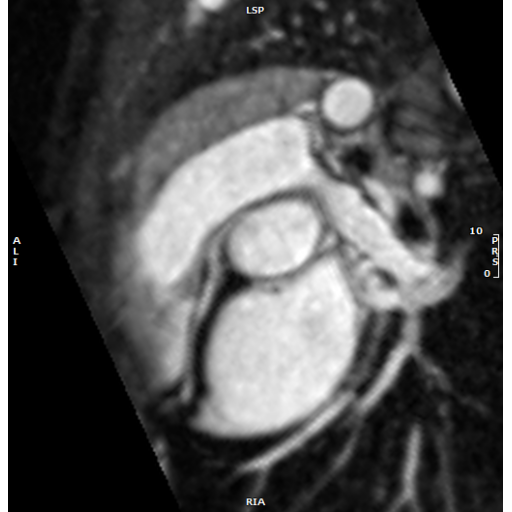

Anomalous RCA from above the left sinus imaged with IR-FLASH iNAV after ferumoxytol in same sedated 4 year old.

Anomalous RCA from above the left sinus imaged with IR-FLASH iNAV after ferumoxytol in same sedated 4 year old. Anomalous RCA from the left sinus imaged with T2-prep SSFP iNAV after gadavist in a non-sedated 13 year old.